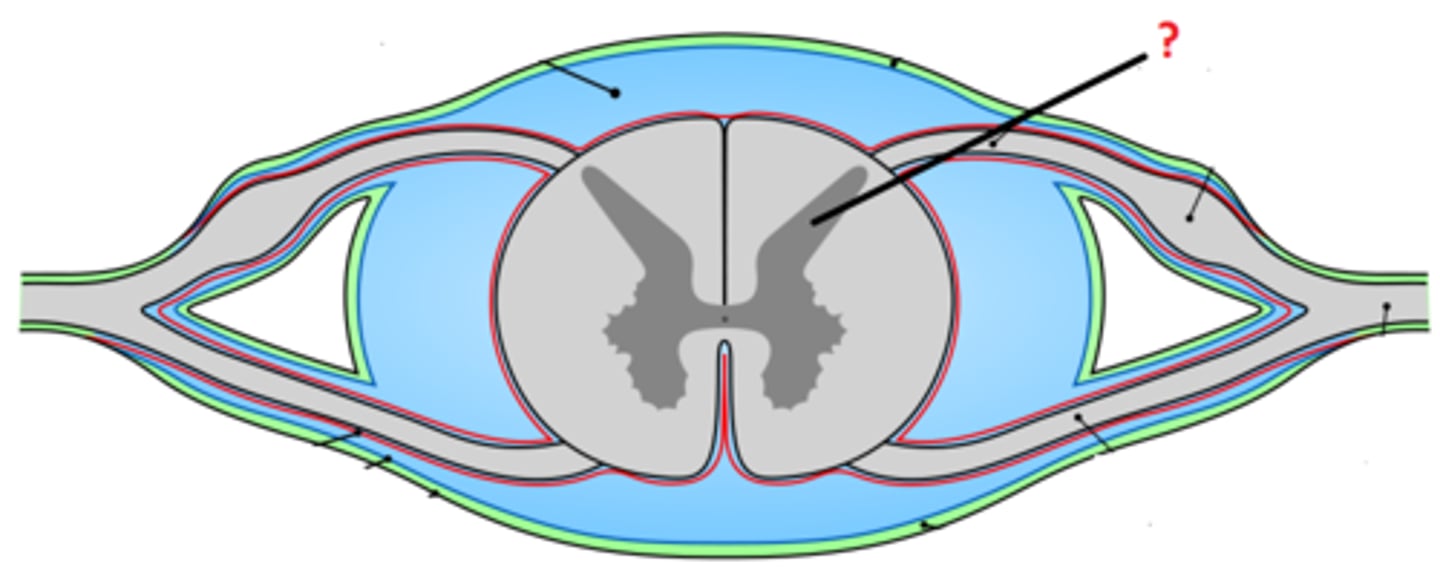

spinal meninges

dura mater, arachnoid mater, pia mater (PAD to protect the spinal cord from deep to superficial)

dura mater (spinal cord)

thick, outermost layer of the meninges; 5 on image

arachnoid mater (spinal cord)

middle weblike layer of the meninges; 4 on image

pia mater (spinal cord)

thin, delicate inner membrane of the meninges; 3 on image

central canal of spinal cord

center of spinal cord which contains cerebrospinal fluid

posterior median sulcus

a shallow vertical groove dividing the spinal cord throughout its whole length in the midline posteriorly.

anterior median fissure

a groove along the anterior midline of the spinal cord that incompletely divides it into symmetrical halves

gray matter of the spinal cord

cell bodies, dendrites, and unmyelinated axons arranges in a butterfly shape with anterior and posterior "horns"

posterior (dorsal) horns

contain axons of sensory neurons and cell bodies (sensory nuclei) of interneurons